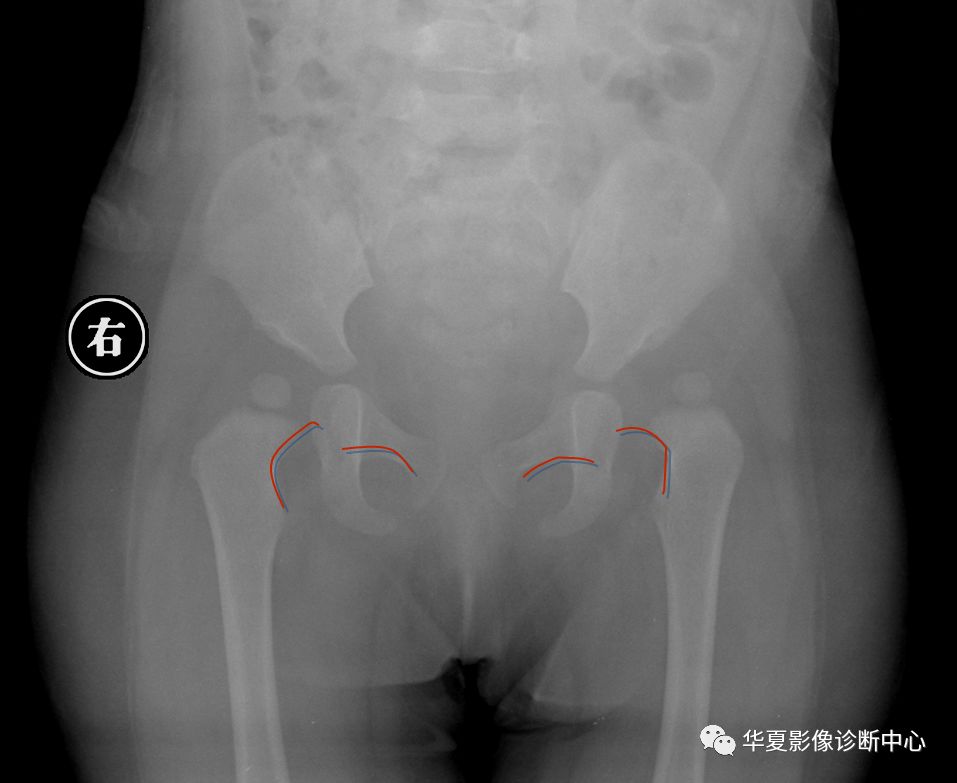

6. Shenton线:

正常闭孔上缘弧形线与股骨颈内侧弧形线相连在一个抛物线上,称为Shenton线,髋脱位、半脱位病例,此线完整性消失。